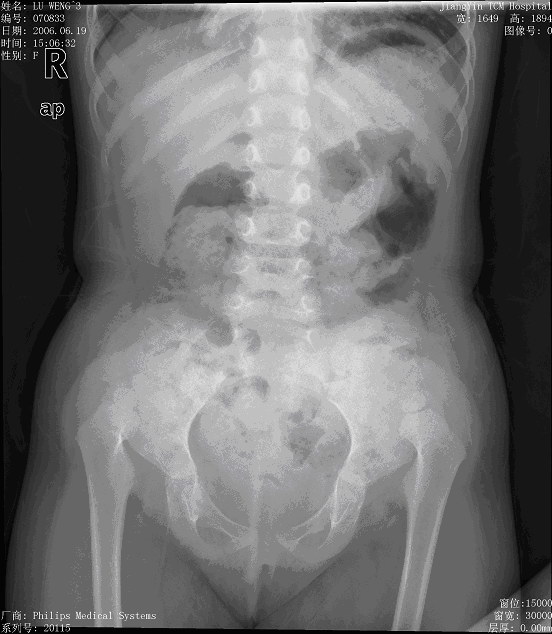

标题: X0847:给大家看一个双侧髋关节脱位的片.

女3岁,因走路不稳来院检查.发现双侧髋关节脱位.髋关节脱位没什么稀奇的,我要请教大家的是:这个病人它没有明显的髋臼,它是靠什么来支撑的?

是先天性髋脱位,现在是和髂骨形成假关节,同时由关节囊及附属韧带来支持。

先天性髋关节脱位一般都与髂骨形成假关节,因为它周围有韧带和关节囊起保护作用.